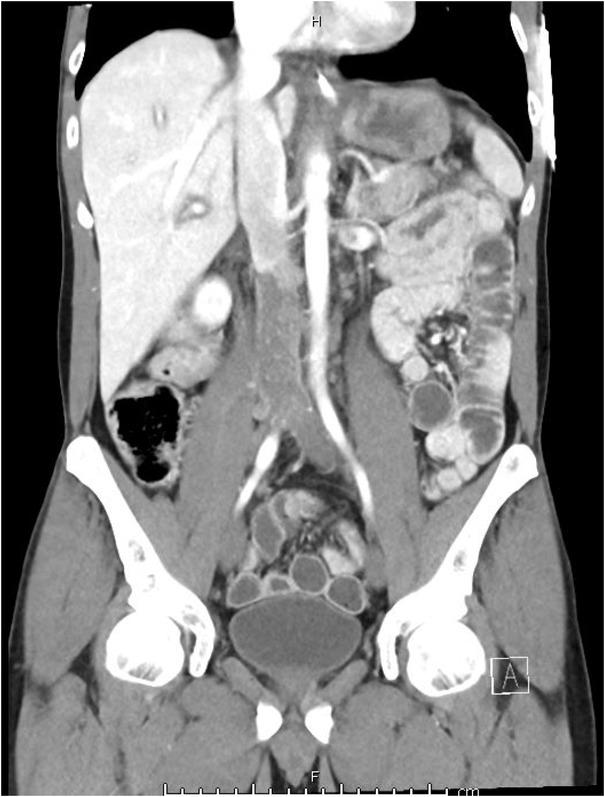

A testicular mass on CT and elevated levels of alpha-fetoprotein revealed a diagnosis of germ cell tumour, which had not been previously diagnosed. CT also demonstrated a significant burden of thrombus within the IVC and iliac veins (Figure 2), with an associated aortocaval lesion in direct continuity with the IVC.

CT abdomen and pelvis coronal image demonstrating extensive iliocaval thrombosis